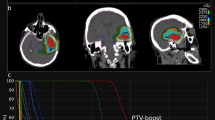

Our purpose was to present the clinical feasibility of TBI with helical tomotherapy (HT) in four patients with AML. Treatment planning, delivery, dose verification and summation, toxicity and patient outcomes for each patient are presented. TBI prescription was set in such a manner that 80% of the clinical target volume received 12 Gy in six fractions, at two fractions per day. Dose reconstruction was carried out by recontouring the regions of interest in the daily pretreatment megavoltage computed tomography of each individual fraction and calculating its corresponding dose. A deformable registration model was used for dose summation of all individual fractions. Differences between planned and delivered doses were calculated. Average planned and delivered doses to the regions of interest differed by up to 2.7%. TBI toxicity was limited to radiotherapy oncology group grade 1 dermatitis in all patients and grade 1 headache in one patient. Two patients are alive with no evidence of disease and no GVHD. Two patients died of GVHD, but there was no evidence of disease at the time of death. We conclude that HT simplifies the process of TBI. Dose verification is possible with HT showing small differences between plan and delivered doses.